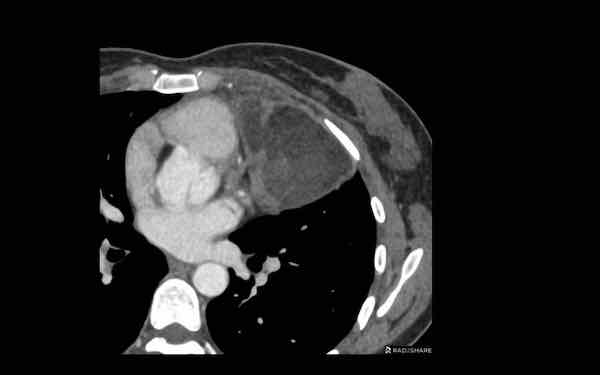

Các hình ảnh này của một bệnh nhân nam 68 tuổi, vừa trải qua phẫu thuật bắc cầu động mạch vành.

Bệnh nhân than phiền khó thở.

Nồng độ D-dimer cao và CT được thực hiện để tìm kiếm thuyên tắc phổi.

Hình ảnh

Có một khối trong trung thất trước mạch máu.

Tỷ trọng là 44